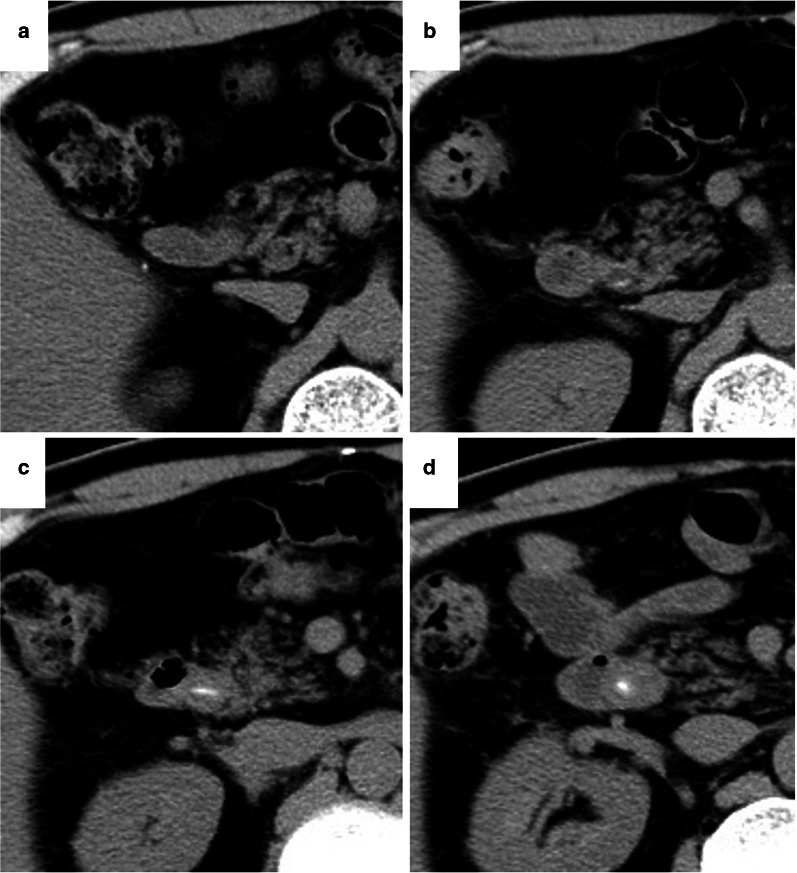

A 70-year-old man was admitted to our hospital for obstructive jaundice. He had undergone distal gastrectomy with Roux-en-Y reconstruction for gastric cancer concomitant with cholecystectomy for cholecystolithiasis approximately 10 years prior at a different hospital. The pathological staging of his gastric cancer was SS, N0, M0, stage IB. Gastric cancer recurrence was not detected during postoperative surveillance by computed tomography (CT) imaging or blood examination (Fig. 1a). In November 2016, further examination for repeated episodes of epigastralgia revealed the presence of obstructive jaundice. The patient’s serum total and direct bilirubin levels were 4.2 and 2.4 mg/dL, respectively. Moreover, hepatobiliary dysfunction was detected and the patient’s serum alkaline phosphatase, aspartate aminotransferase, alanine aminotransferase, and gamma-glutamyl transferase levels were 474 IU/L, 264 IU/L, 496 IU/L, and 676 IU/L, respectively. C-reactive protein was elevated at 11.2 mg/dL. CT examination revealed CBD dilatation with a high-density area (Fig. 1d). On a series of surveillance CT images, a spotted high-density area in the CBD was confirmed in a retrospective analysis following the onset of cholangitis (Fig. 1b, c). Multi-plane reconstructed (MPR) CT revealed a CBD stone along the length of the CBD that contained a needle-shaped calcification density at its center (Fig. 2). The patient was diagnosed as acute cholangitis concomitant with CBD stone. Gastroenterologists at our center and from a nearby hospital deemed that it would be difficult and tentative to perform endoscopic therapy to remove the stone through the Roux-en-Y reconstructed intestine. Therefore, the surgical procedure was adopted as quick and reliable treatment option and was performed using the upper median laparotomy approach. A severe adhesion, resulting from prior surgeries (namely distal gastrectomy and cholecystectomy), was found between the liver and the hepatoduodenal ligament. Even though the CBD was carefully exposed to adhesiolysis, a choledocoduodenal fistula was not detected. Lithotomy with choledochotomy was performed to remove one fragile bilirubin stone that had formed around a 3-cm, needle-shaped fish bone (Fig. 3). The choledochotomy was closed by interrupted sutures using a polyglactin 910 suture. CBD drainage was not performed. The needle-shaped foreign body was diagnosed as a fish bone by histological hematoxylin and eosin staining and infrared absorption spectrophotometry (Fig. 4). The patient’s postoperative course was uneventful and free of adverse events. The patient was discharged on postoperative day 21. No recurrence of a CBD foreign body was identified over the 4 years since the surgery.

In various reports, CT imaging has been useful to identify aspirated fish bones [ref. 9, ref. 12, ref. 28]. In our case, the fish bone in the CBD was visible on coronal plane MPR CT images performed at the onset of the cholangitis. On images of the axial plane CT, only a dot-like high-density area was observable, even though it could not be confirmed as an abnormality as the patient did not develop any symptoms. In particular, it was difficult to detect the very small spotted high-density area on the axial plain, which was performed before the cholangitis as a periodical examination. Today, owing to improvements in CT processing speed and resolution, CT reconstructed imaging could be routinely performed in cases with biliary system abnormalities.